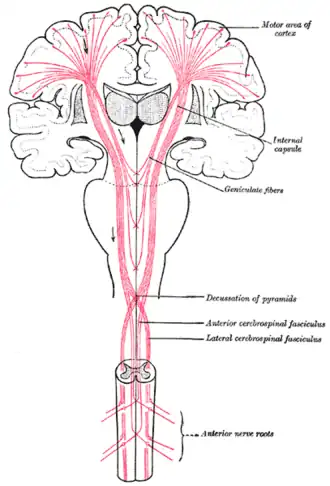

In order to understand functional defects observed in Lou Gehrig's disease, the loss of movement control has been traced to specific organs, cell types and individual genes. What are the structural components of the nervous system that are specifically involved in control of movement? Up until the middle of the 19th century, diseased brain and spinal cord tissue could generally only be productively analyzed in terms of alterations in the gross anatomy. Although microscopy was then allowing advances in cellular pathology -the association of disease processes with structural changes in specific cell types of organs- the individual neurons of the brain and spinal cord were generally resistant to meaningful visualization by microscopy.

Anatomists such as Paul Broca were able to associate behavioral defects with structural damage to particular parts of the brain. The part of the brain called "Broca's area" was linked to disruption of speech generation without any block in the ability of patients to comprehend language. Broca's area is connected to nearby parts of the brain that contain cells with axons that carry movement control signals to the spinal cord. The bundles of movement control axons degenerate and are smaller than normal in patients with Lou Gehrig's disease.

About a decade after Broca's area was recognized as a movement control area of the brain, Vladimir Betz used a new technique, the Golgi stain, to identify a type of giant pyramidal shaped cells that are movement control cells of the brain. These "Betz cells" are among the largest neurons of the human brain and they are depleted from the brains of patients with Lou Gehrig's disease.

The Nobel Prize-winning research on RNA inhibition might lead to new treatments for patients with Lou Gehrig's disease due to dominant mutations in the superoxide dismutase gene. Reduction in the level of the superoxide dismutase enzyme coded for by the mutant gene has been studied in animal models of Lou Gehrig's disease. Superoxide dismutase is a major protein in the brain and spinal cord, so it is a challenge to find ways to significantly reduce production of this protein in the movement control neurons [3]. "RNA inhibition", often abbreviated "RNAi", is a normal process inside cells by which ribonucleic acid can lead to reduced levels of a specific protein. The specificity arises due to base-pair complementarity between the inhibitory RNA and target nucleic acids that are involved in producing a specific protein.

Working with laboratory mice as an experimental model system for the human disease ALS, Miller et al showed that loss of muscle function could be slowed using RNA interference[5]. This result was obtained by using a virus to induce RNA interference in neurons. Recent results indicate that disease-causing superoxide dismutase that is present in non-neuronal cells also contributes to the death of movement control cells and progression of the disease[6]. These results from laboratory experiments suggest that if RNA-induced inhibition of mutant superoxide dismutase can be induced in the correct cells of the brain and spinal cord, it might be possible to slow progression of Lou Gehrig's disease in humans.